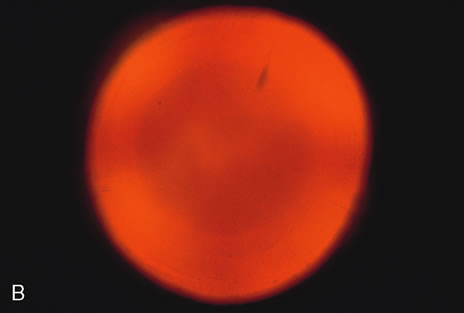

to each other (Figs. 2, 5, 6, and 7).   Fig. 2. Brunescent (brown) nuclear cataract using (A) narrow beam slit illumination and (B) retroillumination. The cataract is best seen by direct slit illumination. In

retroillumination, as seen in this image, the outline of

the nuclear cataract may be seen due to its increased refractive index, although

the cataract does not cast any shadows. Because of its central

location, this cataract may cause distortion of images early in their

development. Fig. 2. Brunescent (brown) nuclear cataract using (A) narrow beam slit illumination and (B) retroillumination. The cataract is best seen by direct slit illumination. In

retroillumination, as seen in this image, the outline of

the nuclear cataract may be seen due to its increased refractive index, although

the cataract does not cast any shadows. Because of its central

location, this cataract may cause distortion of images early in their

development.